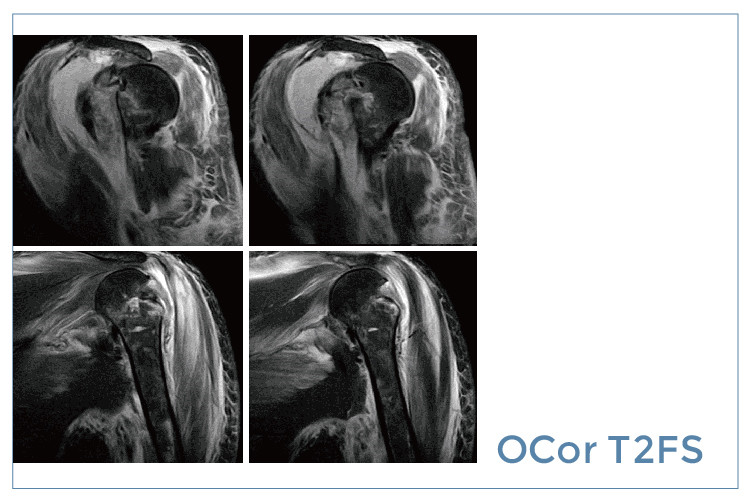

【朗润影像档案】磁共振影像病例分享(编号20190830)